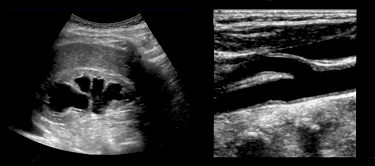

Ultrasound can feel intimidating at first. The images are unfamiliar, the controls seem endless, and many teaching environments assume prior knowledge that newer learners simply haven’t had the chance to build yet. We do things differently.

You’ll learn how to hold the probe with purpose, orient yourself confidently within anatomy, and recognize normal structures before pathologic ones are ever introduced. Doppler is taught as part of this same continuum—not as an advanced add-on, but as a natural extension of understanding motion, flow, and physiology at the bedside.

This foundational course matters because it teaches you how to see—not just where to place a probe. By combining guided bedside scanning with focused clinical reasoning, you’ll move from memorizing textbook images to understanding how anatomical motion, physiology, and patient context inform decision-making. If your goal is to make ultrasound a reliable extension of your clinical exam, this course gives you the skills to do it confidently and consistently.